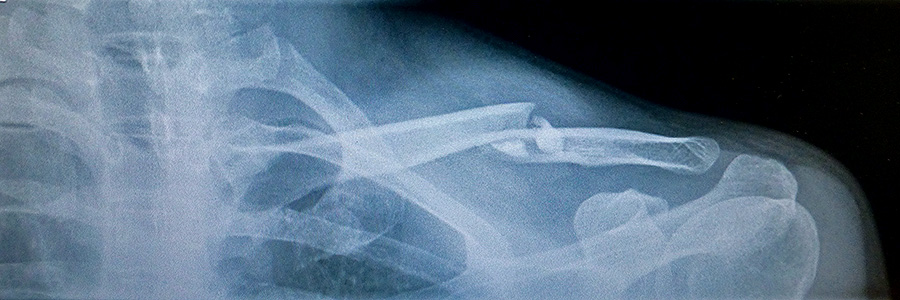

i arrived at 3C yawkey right at 8:30. i took off my jacket in the waiting room. after 10 minutes of waiting an attendant came in and brought me into one of the exam rooms. there was a computer with my x-ray photos (from last week) on the screen. i waited another 15 minutes before a resident came me and asked me to take my shirt off so he could do a quick check of my condition. he left me with some medical forms to fill (kind of weird, given that it should all be in the MGH database already) while i waited for the doctor to show up.

the basic gist of what they said was this: i was healing normally, there seems to be no complications, and i have the full use of my arm, it just depends on how much pain i can tolerate. doctor vrahas said there wasn't anything i could do to stop the healing process. one of my concerns was looking at the x-rays and feeling it for myself, there seemed to be a very large and hard sticking out from the breakpoint, like maybe the bones weren't aligned properly and needed to be set. the doctor told me this was quite normal, that a lump forms around the fracture site, but over time the lump gets reabsorbed and the bone goes back to normal. i still had questions, but it seemed like i had nothing to worry about, with the underlying message that was all very normal. the doctor even pressed down on the lump and i was surprised there was no pain when he did it, because i always felt that spot was still broken, especially since i can move my arm in such a way that i can feel something grinding there. the doctor even said i didn't have to wear my arm sling anymore, unless i wanted to. with that vrahas was on to another patient. the resident stayed behind, asked if i needed help getting dressed. he also added that if i was looking for a perfect place to break a bone and have it heal back to normal, i couldn't have picked a more perfect spot.